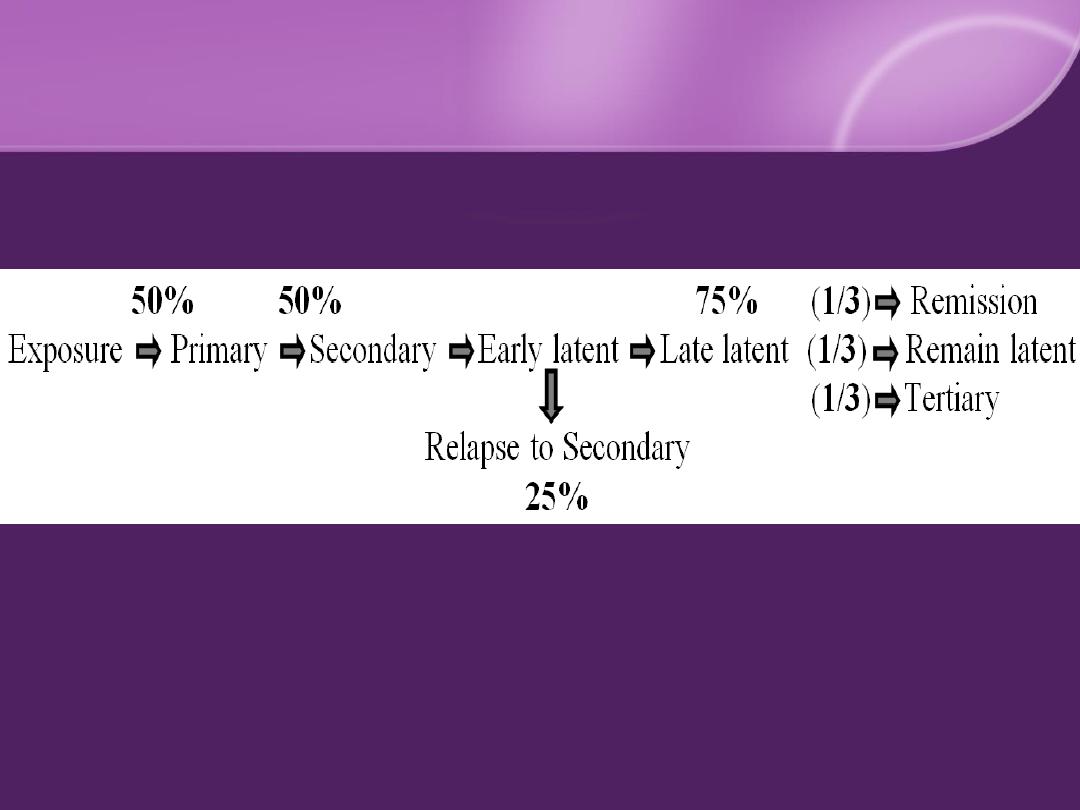

Natural Course of Syphilis

Primary Syphilis (chancre) :

The syphilitic ulcer (

chancre

)

IP: 9-90 days (3 weeks in

50%

)

Solitary

,

painless

,

hard

,

clean base (

50%

)

Painless, hard, discrete regional LN.

Secondary Syphilis: